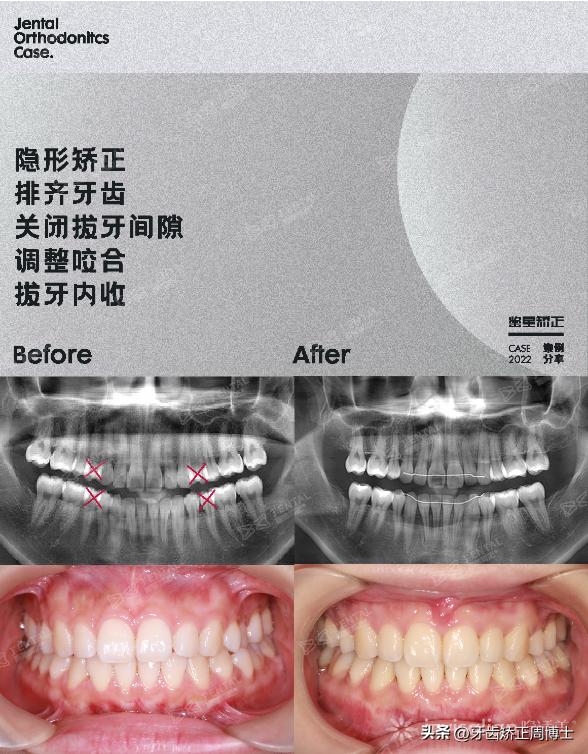

案例概况:高角型骨性前突+下巴后缩+露龈笑

经过面诊,我发现她骨性前突下巴后缩比较严重,有3度,并且伴随着3度的露龈笑。从侧位片上看,她属于高角面型,下颌骨条件非常好,升支、水平支长度都够长,颏部形态发育的也比较翘,很适合MIA矫正。下巴在逆旋以后,侧貌会很漂亮。

方案设计:拔除4颗正畸牙+9颗骨钉+70副牙套

方案设计拔除4颗正畸牙,使用9颗骨钉,一共设计了70副牙套。原计划三年的案例,在她高自律高配合之下提前了十个月毕业。整个矫正过程用了2年2个月,从头到尾没用过一颗托槽。